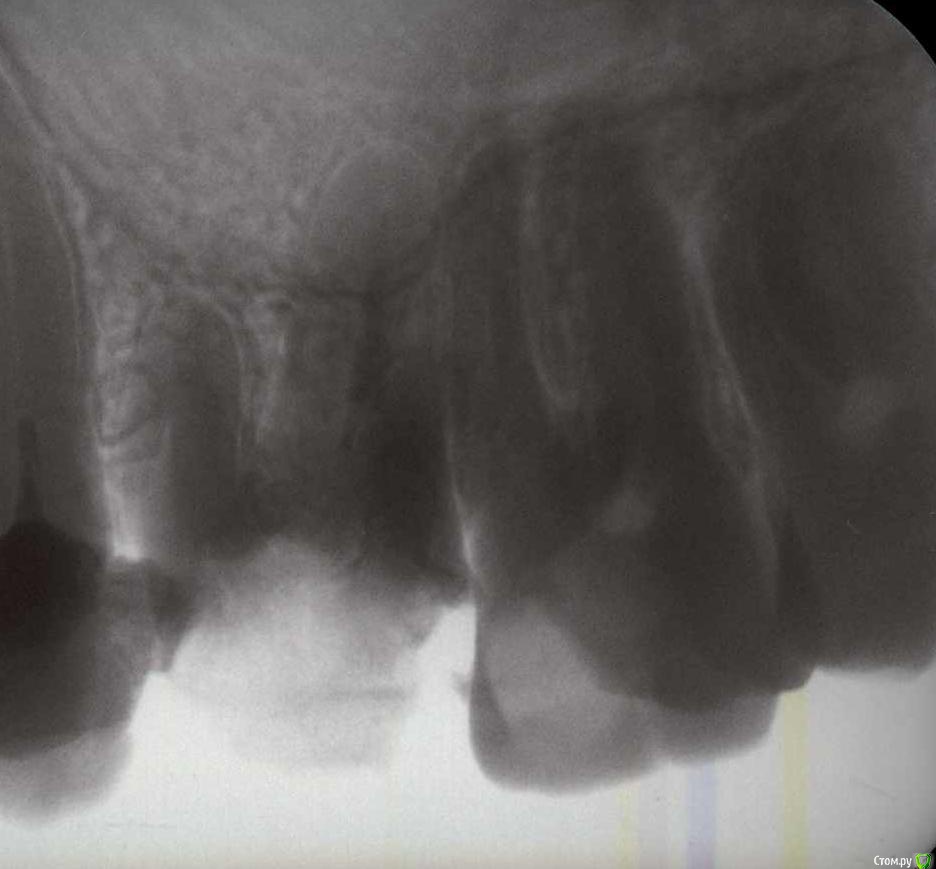

stomt Опубликовано 3 апреля, 2016 Автор Поделиться Опубликовано 3 апреля, 2016 (изменено) Вот здесь скан нового ренгена этих зубов. Ренгенолог (другой) сказала, что здесь все видно. Не знаю насколько это соотвествует действительности, но очевидно что качество снимка здесь намного лутче. Изменено 3 апреля, 2016 пользователем stomt Ссылка на комментарий

stomt Опубликовано 3 апреля, 2016 Автор Поделиться Опубликовано 3 апреля, 2016 Здесь я может что-то непонимаю или как. Пятый это "малый" премоляр - у меня запломбированый. Далее -- первый "большой" моляр (6-ой согласно скачаной нумерации) -- это как я писал полностью высверленный уже годами, и перепломбированный неединожды (сейчас без пломбы) А вот следующий моляр (7ой как-бы) вот он меня и интересует, он дергал,высверленный на 70-80% -- тоже без пломбы (вот внешняя стенка еще толстая, может накладается на менее плотную внутреннюю стенку на рентгене). Вот в нем что с корнями, а то чуствую болевые ощущение очень глубоко. Есть какой то периодонтит? А следующий уже зуб мудрости - с налетом (камнем), хотя предыдущий еще больше с камнем. Ссылка на комментарий

stomt Опубликовано 4 апреля, 2016 Автор Поделиться Опубликовано 4 апреля, 2016 Та куда уже фотографировать. Уже повторно сделали снимок. Я его отсканировал - разве слева два полных премоляра еще есть, но меня интересует два моляра что посредине на этом фото - конкретно тот что справа - за ним только зуб мудрости, который здесь ( и на снимке) на 60-70 % отображен.Ну может чтобы не6 повторятся "пятый" и "шестой" в вашей описи это которых именно зубов из прикрепленного изображения касается - их там четыре (первой и четвертый лиш частично захвачены) Ссылка на комментарий

stomt Опубликовано 4 апреля, 2016 Автор Поделиться Опубликовано 4 апреля, 2016 Так подскажите что там с этим большим зубом что прозрачный в левом нижнем углу? Что атм с корнем -- можно ли еще пломбировать или протезировать? А то завтра иду врачу - и не знаю говорить ли ей об этом зубе - или пусть делает менее важные. Ссылка на комментарий

stomt Опубликовано 19 апреля, 2016 Автор Поделиться Опубликовано 19 апреля, 2016 5-ый самый левый лиш частично на снимке - он запломбирован, 6 - разве культя подойдет (уже 10 лет тому мне говорили об этом - я его только пломбировал), 7-ой здесь обговариваем, "8"- зуб мудрости. Вы мели ввиду 5 -тот что я имею ввиду 6-ой, а "ваш" 6-ой - тот что у меня 7-ой (да и касательно класификации тоже)? Просто хочу понять ваш совет, думаю он не от "фонаря" сделан, только надо правильно сопоставить зубы на снимке. Ссылка на комментарий

stomt Опубликовано 20 апреля, 2016 Автор Поделиться Опубликовано 20 апреля, 2016 1. Ну в общем о пятом где лиш его часть я не спрашивал. Он запломбирован (и это "малый" зуб, и там где у вас надпись это граница между 5ым и 6ым).Шестой - да говорили мне уже давно о вкладке(культе) - а что за твердые ткани вы имеете ввиду?2. Вопрос здесь стоит о 7-ом (том что за шестым), который собственно болит (время от времени), хотя никаких "нагрузок" не имеет. Что там у него с корнями, можно/надо ли протезировать?3. Касательно врача -- она как бы не последний врач - хотя профиль ее касается несколько иной возрастной категории -- но лечит меня (пломбами) более 10 лет. Ссылка на комментарий